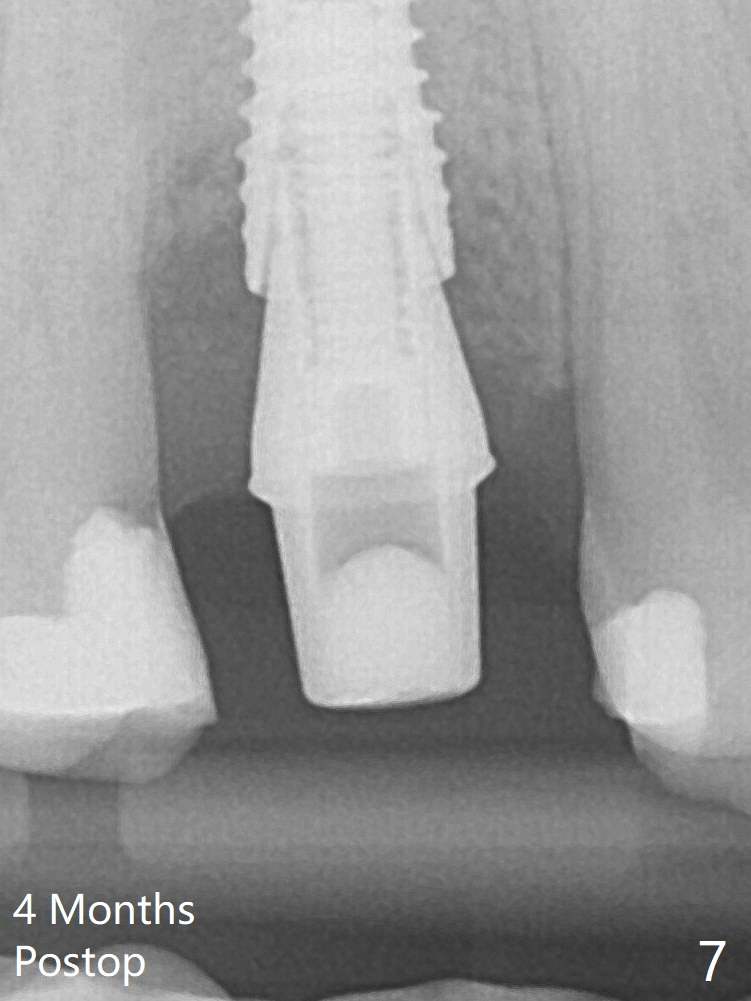

A 3.8x18 mm (definitive) implant is placed with <40 Ncm with the implant plateau apical to the lingual crest (Fig.4 (dashed line: upper border of the buccal defect)). The buccal plate defect is repaired by Vanilla Graft (Fig.6 *) before and after insertion of a 4.5x4(3) mm abutment. The buccal plate defect seems to being repaired 4 months postop (Fig.7).